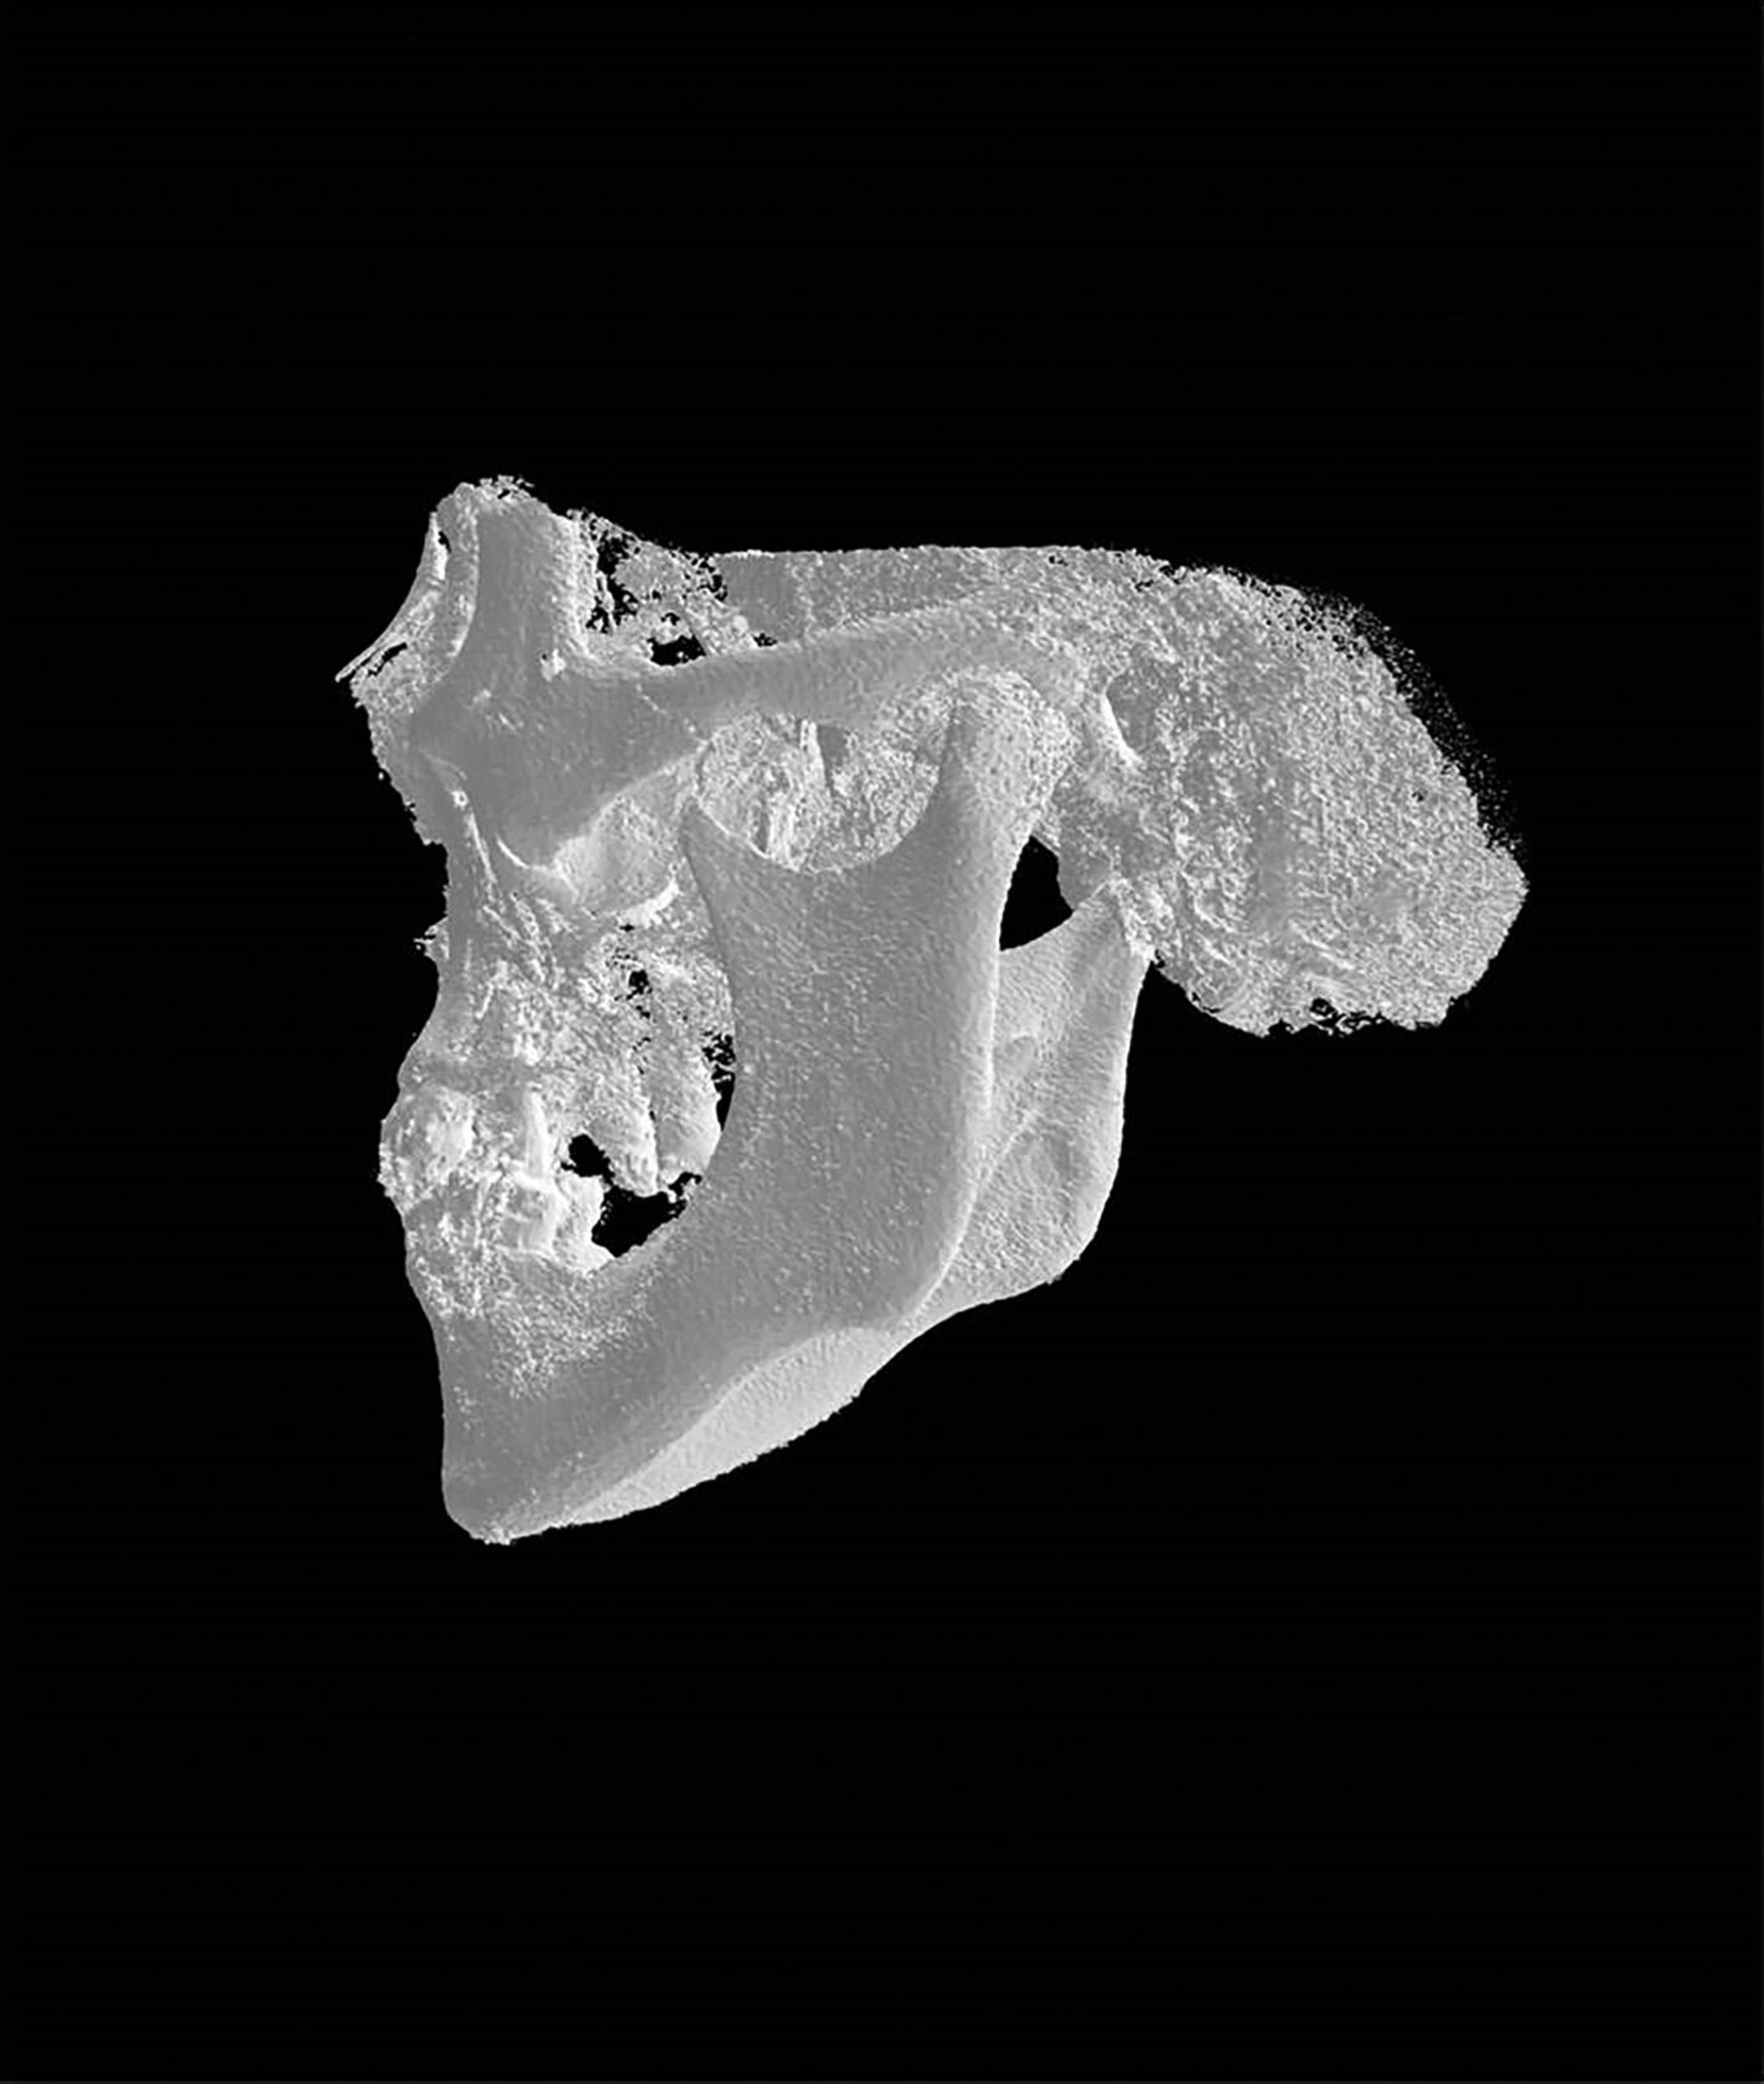

Der postoperative Verlauf gestaltete sich regelrecht ohne Nachblutung oder Wundheilungsstörungen. Die Mini-VAC-Drainage wurde am zweiten postoperativen Tag entfernt. Die Gesichtsmotorik linksseitig im Bereich des Mundwinkels zeigte sich leicht abgeschwächt. Eine postoperative digitale Volumentomografie zeigte die beabsichtigte Verkürzung des linken Processus styloideus (Abbildung 4). Die Entlassung folgte am dritten postoperativen Tag in zeitgerecht gutem Allgemeinzustand.